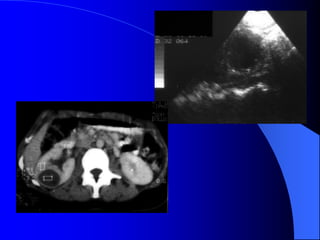

4.2. U bãøtháûn, niãûu quaín vaì baìng quang * Laì loaûi u biãøu mä âæåìng dáùn niãûu aïc tênh, chiãúm 6-10% caïc u tháûn aïc tênh. Caïc yãúu täú nguy cå chênh laì soíi tiãút niãûu, nhiãùm truìng, nghiãûn thuäúc laï, duìng quaï nhiãöu thuäúc phenacetin. Hay gàûp > 50tuäøi, nam = 2næî. * U laình tênh: polyp, hay gàûp âäü tuäøi 20-40. * U aïc tênh: chuí yãúu Carcinome tãú baìo chuyãøn tiãúp (85%), ngoaìi ra Carcinome tãú baìo vaíy (15%). Di càn ung thæ âãún âæåìng dáùn niãûu hiãúm gàûp. * U âæåìng dáùn niãûu hay gàûp theo thæï tæû åí baìng quang, bãø tháûn, niãûu quaín.

- NÂTM + Âäúivåïi thãø thám nhiãùm coï hçnh aính heûp, båì khäng âãöu, thæåìng gáy æï næåïc. + Âäúi våïi thãø suìi, coï hçnh khuyãút saïng trong âæåìng dáùn niãûu, båì coï thãø khäng âãöu, coï thãø gáy æï næåïc âæåìng dáùn niãûu phêa trãn. Cáön phán biãût våïi cuûc maïu âäng vaì soíi KCQ. ٠Soíi vaì maïu cuûc di chuyãøn vë trê, coï viãön caín quang bao quanh. ٠Maïu cuûc thay âäùi hçnh daûng theo thåìi gian. ٠U âæåìng dáùn niãûu (bãø tháûn, niãûu quaín, baìng quang) coï hçnh aính chán baïm vaìo thaình, nåi khäng coï viãön TCQ bao quanh u.

- Siãu ám Khoïcháøn âoaïn u bãø tháûn, niãûu quaín nãúu khäng coï æï næåïc âaìi bãø tháûn niãûu quaín. U baìng quang trãn siãu ám tháúy hçnh tàng ám trong baìng quang coï næåïc tiãøu räùng ám. Siãu ám coï thãø tháúy mæïc âäü xám láún thaình baìng quang vaì ngoaìi thaình baìng quang.

- Càõt låïpvi tênh Hçnh aính u giaím tè troüng so våïi nhu mä tháûn vaì tàng tè troüng sau khi tiãm TCQ. CLVT coï thãø tháúy: Maïu cuûc vaì soíi trong âæåìng dáùn niãûu coï tè troüng cao hån u (20-30UH). Soíi 100 - >1000UH tuìy thaình pháön cáúu taûo vaì maïu cuûc 50-70UH. U bãø tháûn coï thãø thám nháûp nhu mä laìm thay âäøi båì tháûn, coï thãø laìm heûp tàõc âæåìng baìi xuáút, giaîn ÂBT, coï thãø phaït hiãûn âæåüc trãn NÂTM. CLVT phaït hiãûn u bãø tháûn xám nháûp nhu mä tháûn dãù hån, âäöng thåìi phán biãût âæåüc våïi u nhu mä tháûn xám láún bãø tháûn.